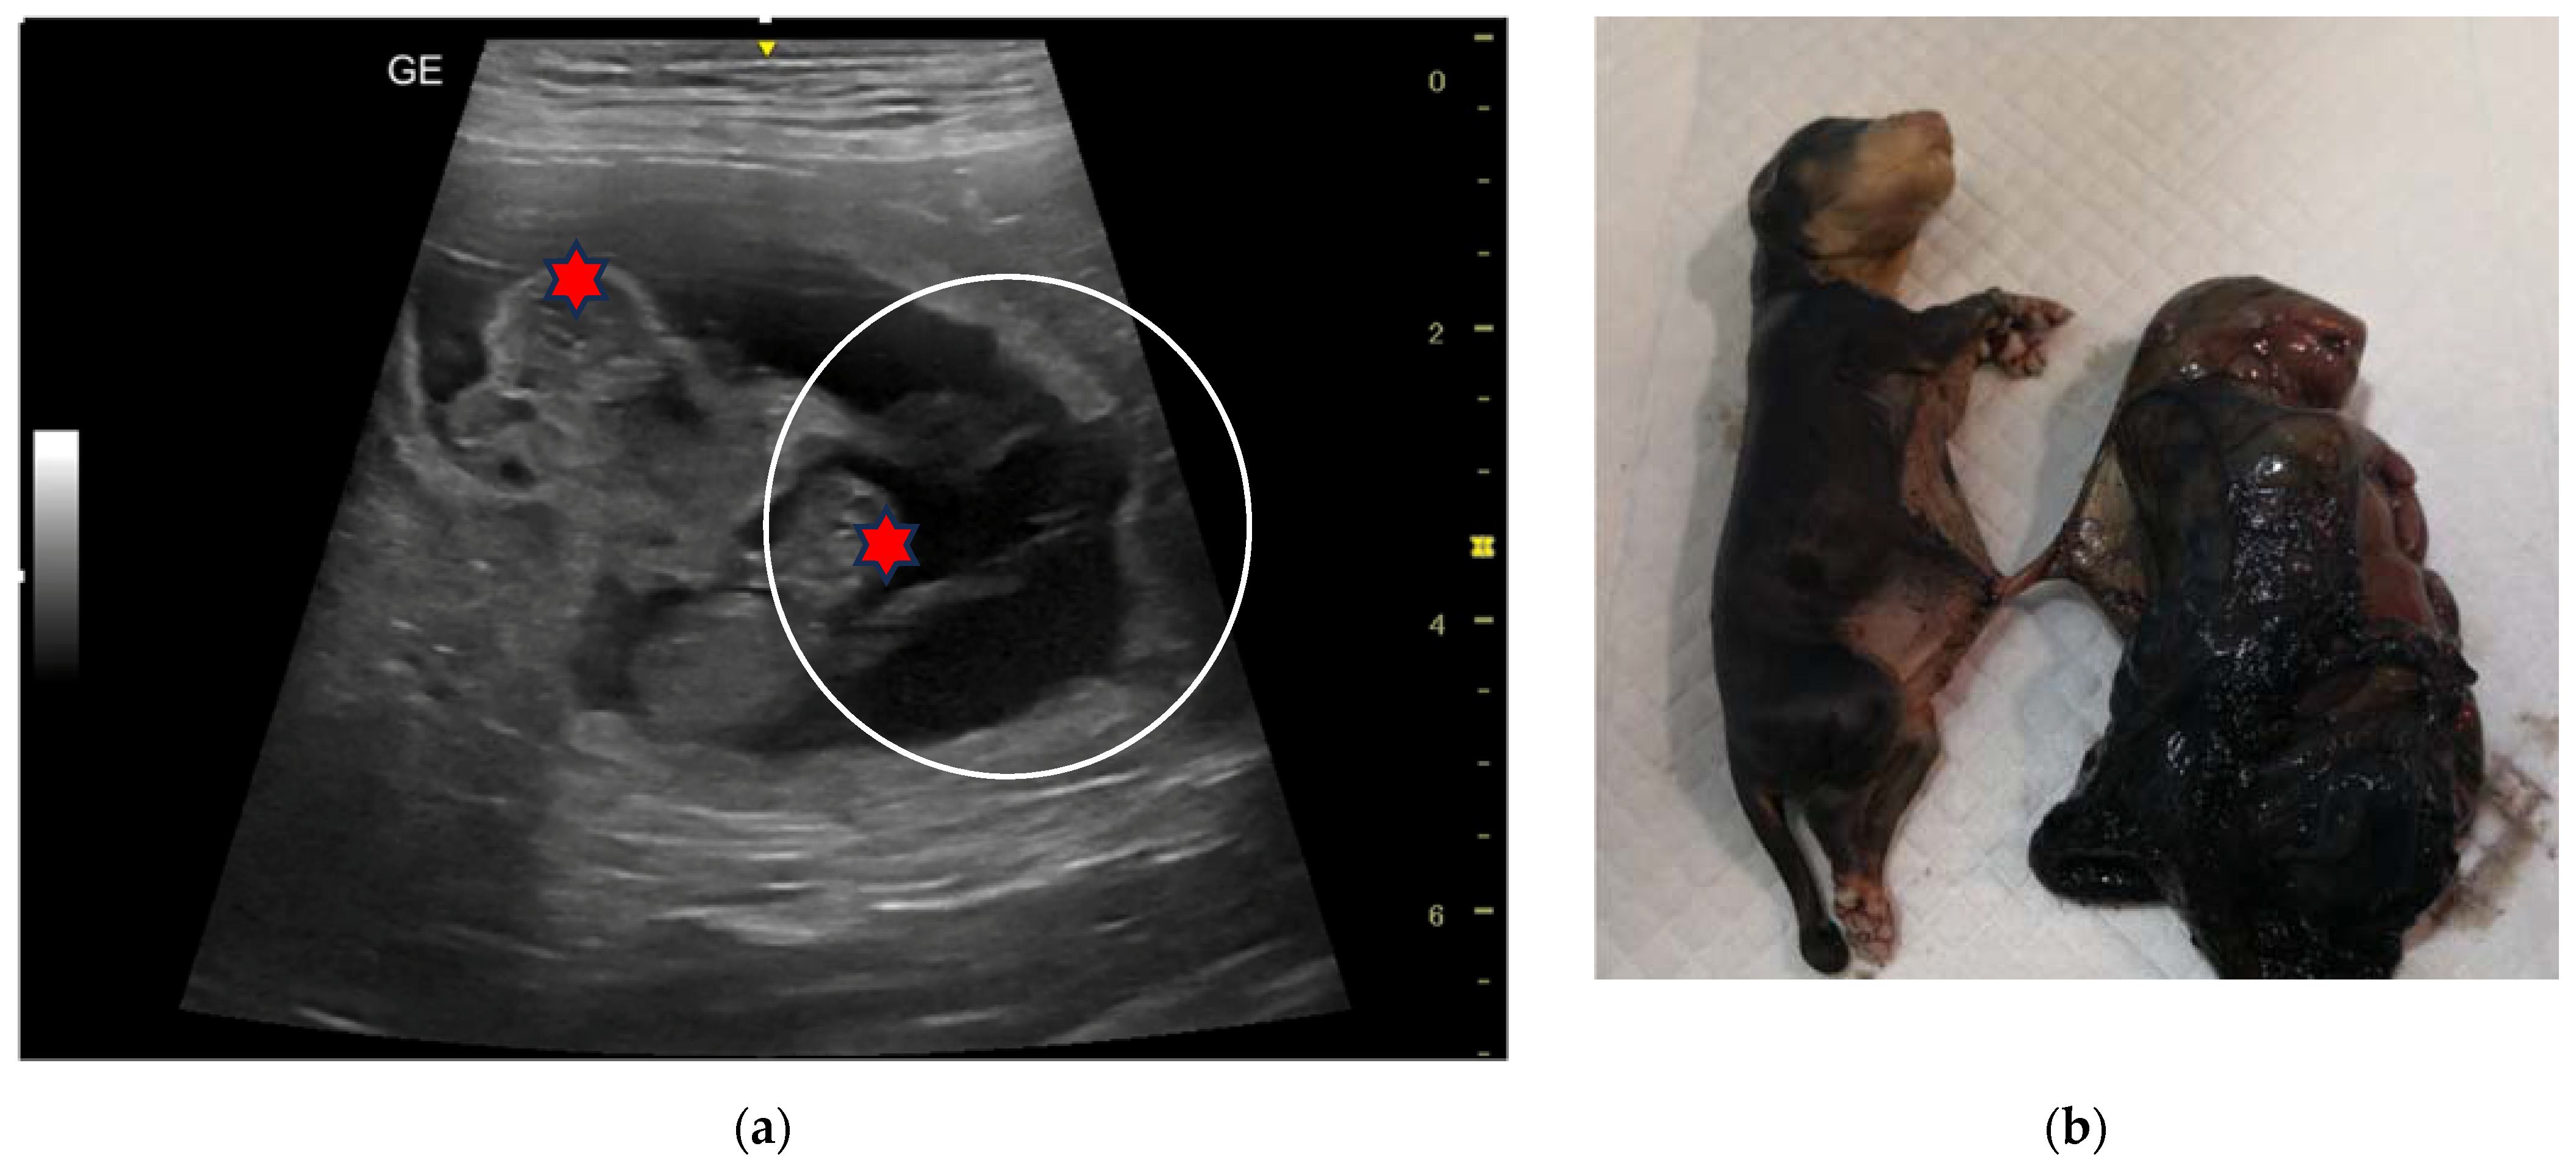

| 5C | 3-year-old Australian Shepherd female dog | 23, 30, 37, 44 and 51 | 12 | Monochorionic twins, morphologically comparable to the other embryos/foetuses. | Natural delivery, dystocia, C-section. Ten puppies alive and two dead twins of the opposite sex. | |

| 6C | 5-year-old Rottweiler female dog | 45 and 55 | 4 | Monochorionic twins, morphologically comparable to the other foetuses; foetal death of the twins. | Natural delivery of two puppies, C-section, and extraction of the twins. | |